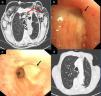

(a) Significant mediastinal and subcutaneous emphysema; (b) LUL lobectomy surgical stump with a 3mm bronchial fistula in the upper area; (c) bronchopleural fistula closure after instillation of Glubran® 2; and (d) resolution of mediastinal and subcutaneous emphysema on follow-up chest CT, 6 months after instillation of the bronchial sealant.

We report the case of an 80-year-old man, active smoker, COPD, GOLD B, who underwent left posterolateral thoracotomy with lobectomy of the left upper lobe (LUL) and systemic lymph node resection, with a diagnosis of squamous lung cancer, stage pT2aN0M0. Two weeks after the intervention, the patient presented progressive subcutaneous and mediastinal emphysema, with significant facial edema, but no upper airway compromise (Fig. 1a). During the endoscopic examination with flexible bronchoscope, a 3mm fistula was observed in the LUL lobectomy stump wound (Fig. 1b). In view of the endoscopic findings, persistent air leak, and worsening subcutaneous emphysema, the fistula was sealed using cyanoacrylate, as follows: 1ml N-butyl-2-cyanoacrylate+metacryloxisulfolane (Glubran® 2 Ref.G-NB-2, GEM srl, Italy), applied using a syringe via a 5 Fr angioplasty catheter (Angiographic Cathether Tempo® Vertebral [VERT] Ref. 451-514H0 Cordis®). Due to the characteristics of the sealant, a safety margin between the distal tip of the catheter and the bronchoscope lens was maintained. Immediately after applying the bronchial sealant, complete closure of the fistula was confirmed (Fig. 1c), the bronchoscope was withdrawn together with the angioplasty catheter placed in the working channel to avoid any sealant remnants entering the interior of the working channel and damaging the equipment during withdrawal. The distal end of the catheter was then closed to avoid any sealant remnant entering the working channel. Five days after the application of Glubran® 2, correct closure of the fistula was confirmed in a second endoscopic procedure; the patient had improved clinically with progressive resolution of the subcutaneous emphysema. The patient was followed up as an outpatient, and a follow-up chest computed tomography was performed 6 months after surgery, confirming clinical stability and complete resolution of the subcutaneous emphysema (Fig. 1d), with no recurrence or other serious long-term complications.